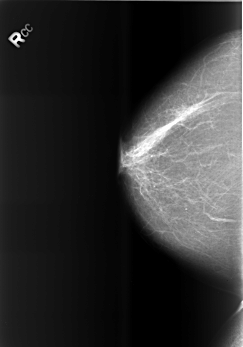

B_3466_1.RIGHT_CC

RIGHT_CC LINES 5552 PIXELS_PER_LINE 3880 BITS_PER_PIXEL 12 RESOLUTION 50 NON_OVERLAY